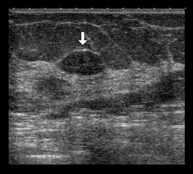

Ecografía mamaria

Es un método de imagen en el que las ondas sonoras crean una imagen de los vasos sanguíneos, tejidos y órganos, incluyendo la mama. La ecografía permite evaluar las anomalías visualizadas en la mamografía o en la exploración clínica, diferenciando asimismo las lesiones sólidas y liquidas (quistes).